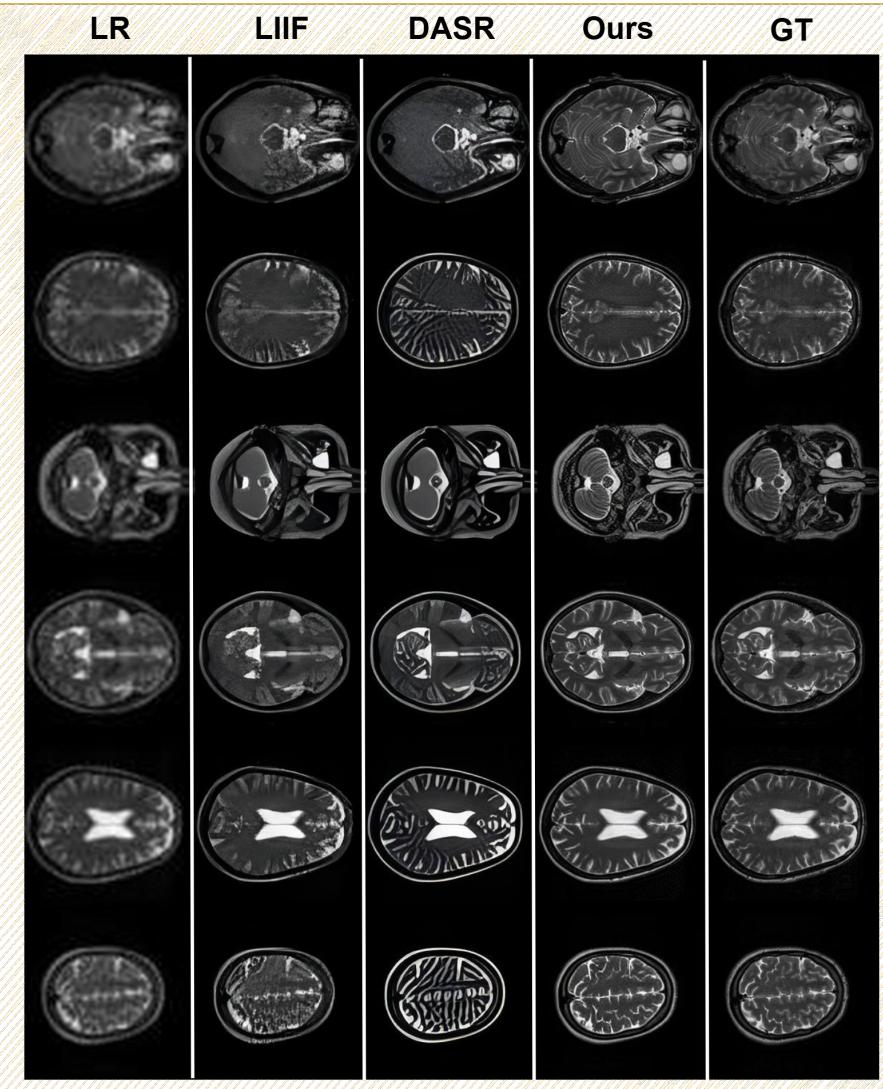

Generation Performance: Super-Resolution

Another critical task is taking a low-quality, blurry MRI and reconstructing it into a high-resolution image.

In Figure 12, compare the “LR” (Low Resolution) column with the “Ours” (HealthGPT) column. The difference is night and day. HealthGPT restores the fine folding patterns of the brain’s cortex that are completely lost in the low-resolution input.

Quantitative results for this task (shown in Table 3 below) confirm that HealthGPT achieves higher Structural Similarity (SSIM) and Peak Signal-to-Noise Ratio (PSNR) than dedicated super-resolution models like SRGAN or SwinIR.